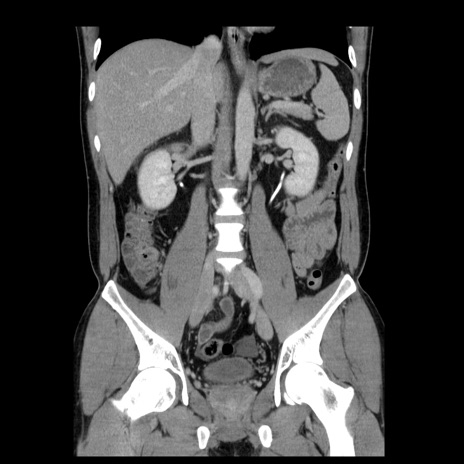

症例4(冠状断像)

【症例】30歳代男性

【主訴】腹痛、嘔吐

【現病歴】昨晩から突然の腹痛あり、その後嘔吐、軟便も出現。腹痛が改善しないため救急搬送となる。2日前にしめ鯖の食事歴あり。

【身体所見】意識清明、苦悶様、BP 135/90mmHg、BT 35.7℃、腹部:平坦、やや硬、心窩部〜臍部に自発痛、圧痛あり、筋性防御+、反跳痛-

【データ】WBC 8100、CRP 0.57